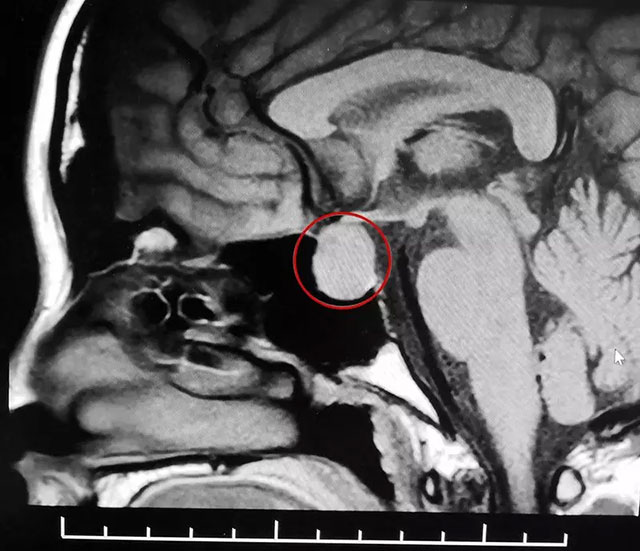

后来一位有经验的医生提醒她去检查一下头部,经头颅磁共振检查,鞍区MRI平扫+增强显示,蝶鞍显著扩大,鞍区见不规则肿块影,大小约1.4*1.7*2.2cm。刘女士被诊断为垂体大腺瘤(垂体瘤超过1厘米就是垂体大腺瘤)。

▲ MR影像检查显示:垂体大腺瘤,超蝶鞍生长